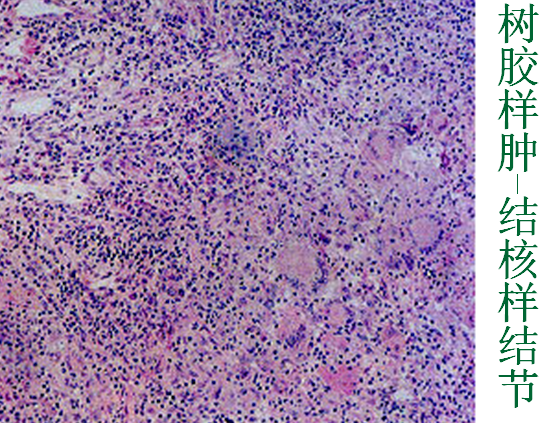

2.树胶样肿(gumma):见于第三期梅毒

可发生于任何器官,最常见于皮肤、粘膜、肝、骨和睾丸。

肉眼:灰白色,大小不一,从镜下才可见到的大小至数厘米不等。质韧有弹性,如树胶。

镜下:结构颇似结核结节,中央为凝固性坏死,形态类似干酪样坏死,坏死灶周围肉芽肿中富含淋巴细胞和浆细胞,而上皮样细胞和Langerhans巨细胞较少,且必有闭塞性小动脉内膜炎和动脉周围炎。

树胶样肿后期可被吸收、纤维化,最后使器官变形,但绝少钙化。